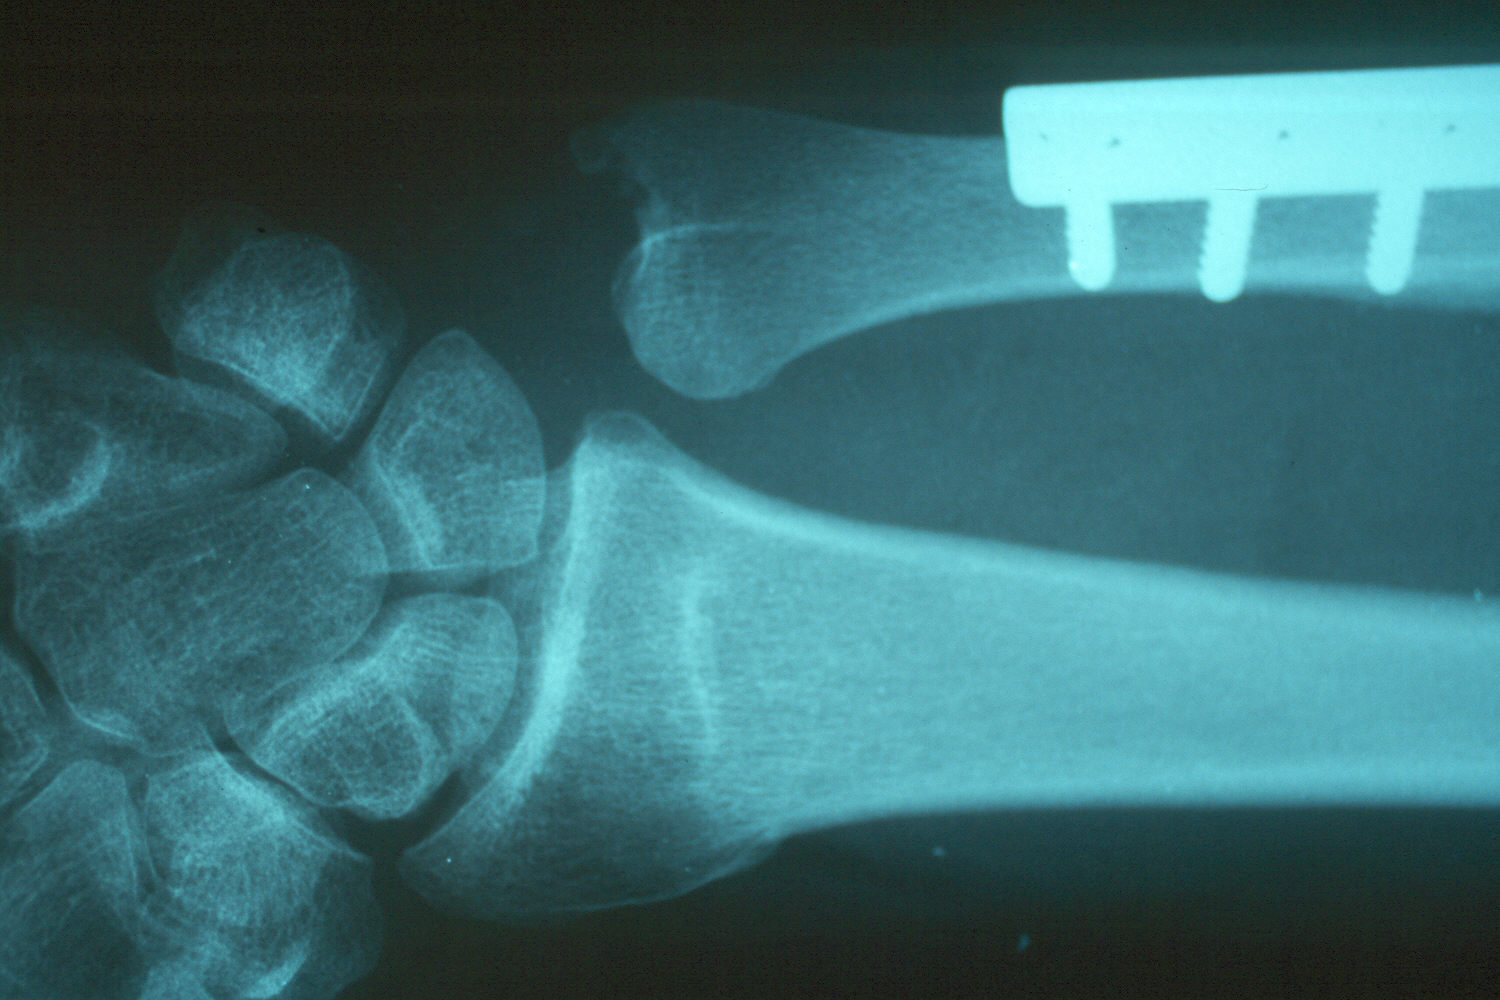

Preoperative radiographs demonstrate radial shortening and relative ulnar lengthening and ulnar carpal abutment.

Late result: proper ulnar alignment restored.